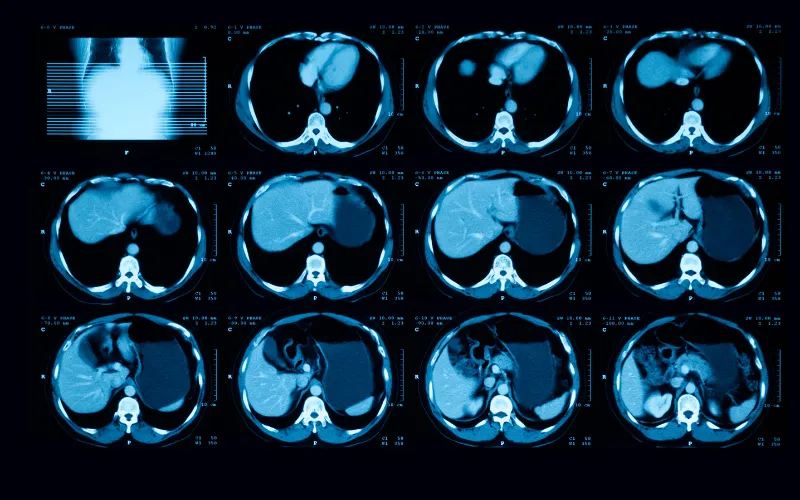

xray of liver tumor

Liver Tumor Center

The Liver Tumor Center at Dana-Farber/Boston Children’s Cancer and Blood Disorders Center cares for patients with all types of liver tumors, both benign and malignant.